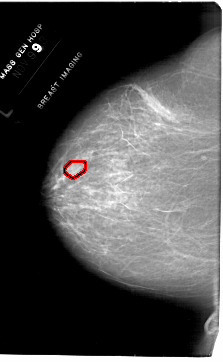

FILE: A_1768_1.LEFT_MLO.OVERLAY

TOTAL_ABNORMALITIES 1

ABNORMALITY 1

LESION_TYPE MASS SHAPE OVAL MARGINS OBSCURED

ASSESSMENT 4

SUBTLETY 2

PATHOLOGY BENIGN

TOTAL_OUTLINES 1

BOUNDARY